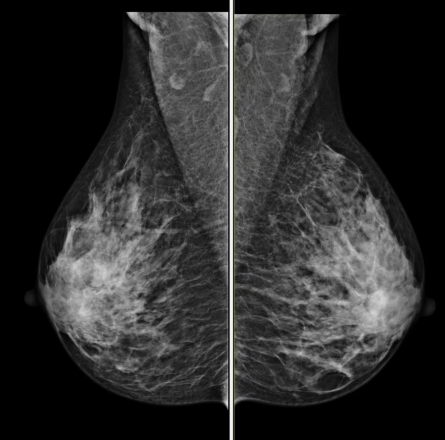

最新一代乳腺钼靶机:专为女性健康保驾护航,通过高分辨率的成像技术,早期发现乳腺病变,提高乳腺癌的早期诊断率。